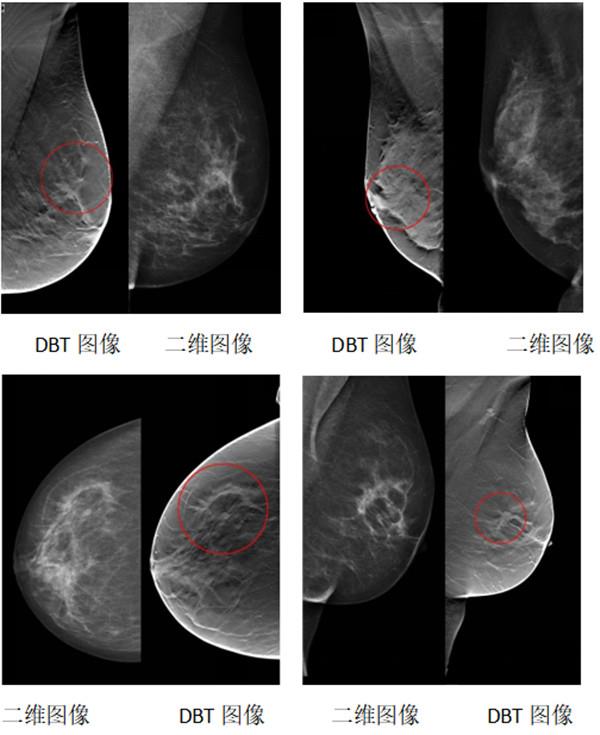

常德市婦幼保健院乳腺健康管理中心2022年引進了目前最先進的數(shù)字乳腺三維斷層合成攝影系統(tǒng)(DBT技術),是湘西北地區(qū)第一臺數(shù)字乳腺三維斷層合成攝影系統(tǒng)(DBT);三維斷層合成攝影(DBT)技術相對于二維數(shù)字乳腺攝影系統(tǒng)優(yōu)勢如下:

一、更清晰地顯示乳腺組織結構,有效避免組織重疊的影像。

二、對于致密型腺體的病人能夠更靈敏地區(qū)分腫瘤細胞與非腫瘤細胞,提高良惡性鑒別能力。

三、能夠發(fā)現(xiàn)二維數(shù)字乳腺攝影因為組織重疊而無法發(fā)現(xiàn)的小腫塊,以及因為組織重疊而影響辨識的毛刺征(惡性乳腺癌的典型表現(xiàn))。

臨床數(shù)據(jù)顯示,三維斷層攝影(DBT)能夠在篩查和診斷中比二維數(shù)字乳腺攝影有更好的敏感性和準確性。其優(yōu)勢使得其在乳腺疾病的診斷和篩查中得到了廣泛的認可和應用。結果顯示,篩查病例的檢出率、假陽性率、復檢率都得到明顯改善。其中,浸潤性乳腺癌的檢出率增加,綜合復檢率降低。